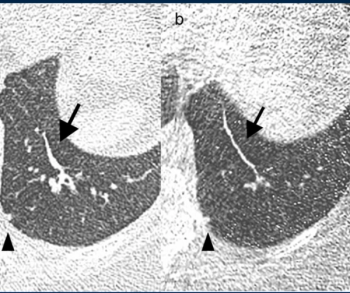

Ultra-low-dose computed tomography (ULDCT) may have similar efficacy as low-dose CT (LDCT) for detecting a variety of pulmonary conditions in people with current or past smoking histories, but had poor detection of ground glass opacification lesions, according to a recent prospective study presented at the Radiological Society of North America (RSNA) conference.